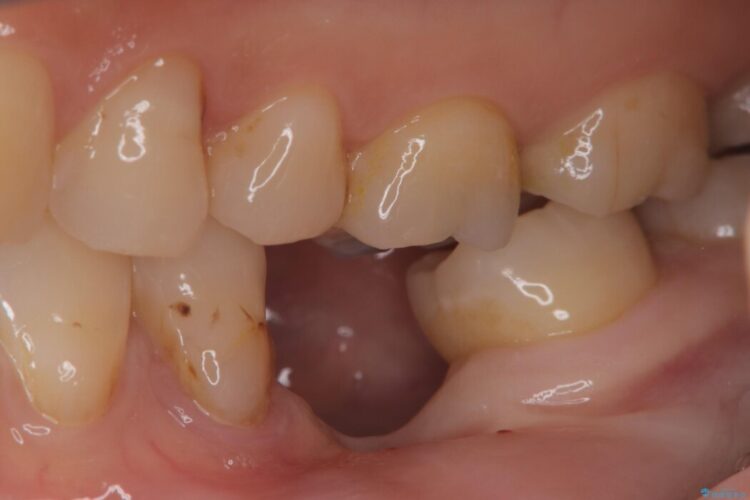

左下奥歯の抜歯後、長期間放置していたために、周囲の骨が吸収してしまいました。 特に垂直的な高さが不足しており、通常の術式ではインプラント埋入が難しい状態でした。

骨を増やす治療は行わず、残っている骨を最大限に活用し治療を行うこととしました。